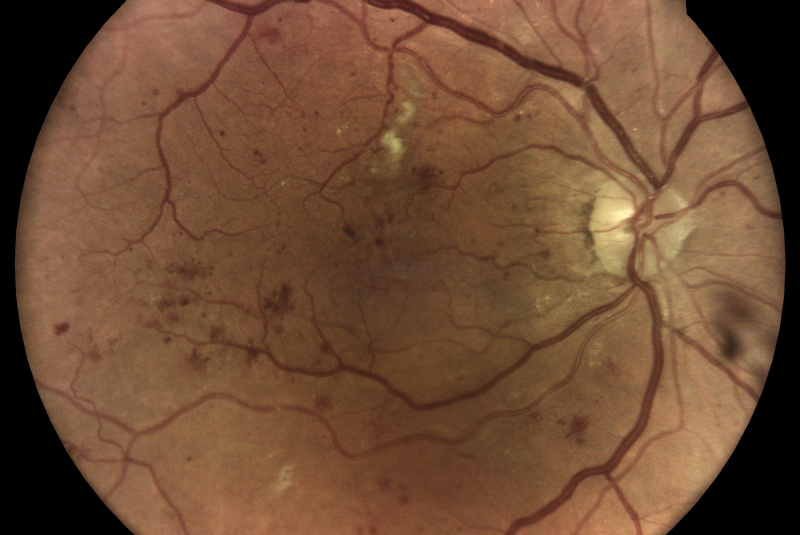

Technológia TrueColor Confocal od iCare prekračuje limity konvenčných zariadení na zobrazovanie fundusu a SLO tým, že kombinuje tie najlepšie výhody z oboch. Jednoducho povedané, fundus fotoaparáty poskytujú vysokú vernosť farieb a systémy SLO produkujú vysokú ostrosť, čistotu, celkovú presnosť a detaily v obrazoch. Keď sa tieto funkcie skombinujú, vytvárajú obraz krajiny sietnice špičkovej kvality vo verných farbách.

Aby bolo možné diagnostikovať a sledovať bežné patológie, ako je diabetická retinopatia, zariadenia na zobrazenie očného pozadia musia byť schopné kombinovať veľké rozlíšenie, vysoký kontrast a vysokú vernosť farieb. To umožňuje zachytiť malé znaky a detaily a rozlišovať medzi jednotlivými zmenami, ktoré by ste mohli inak ľahko prehliadnuť. Zatiaľ čo štandardné systémy SLO majú vysokú jasnosť, ostrosť a kontrast, tradičné fundus kamery ponúkajú vysokú vernosť farieb, konvenčné zobrazovacie riešenia tieto dve veci nekombinujú!

Monochromatické lasery používané v štandardných systémoch SLO môžu vďaka konfokálnemu optickému enginu poskytnúť vysokú ostrosť a vysoký kontrast obrázkov. Na druhej strane nedokážu zachytiť sietnicu v jej skutočných farbách.

Zobrazovacie systémy fundus generujú obrazy s prirodzenými farbami iba vtedy, ak využívajú biele svetlo: to znamená, že všetky vlnové dĺžky viditeľného spektra sú prítomné v osvetľovacom lúči použitom na získanie obrazu sietnice. Na získanom zábere je možné rozlíšiť rôzne farebné detaily.

Naopak systémy využívajúce monochromatické svetelné zdroje, ako sú systémy SLO, používajú na osvetlenie sietnice iba špecifické vlnové dĺžky. Preto poskytujú pseudofarebné zábery, ktorým chýbajú niektoré spektrálne zložky a výsledkom sú chýbajúce informácie alebo farebné artefakty.

iCare sa vyznačuje používaním bieleho svetla LED v kombinácii s konfokálnou optikou, ktorá pomáha získavať vysokokvalitné snímky sietnice so zvýšenou vernosťou farieb.

Fundus kamera iCare DRSplus urobí celkovo 4 vysoko kvalitné True Color snímky (dve z pravého a dve z ľavého oka), ktoré sa automaticky ukladajú na cloud a posielajú sa na spracovanie AI - umelej inteligencii. Report je dostupný ihneď a ten je možné prekonzultovať s pacientom počas tej istej návštevy u lekára.